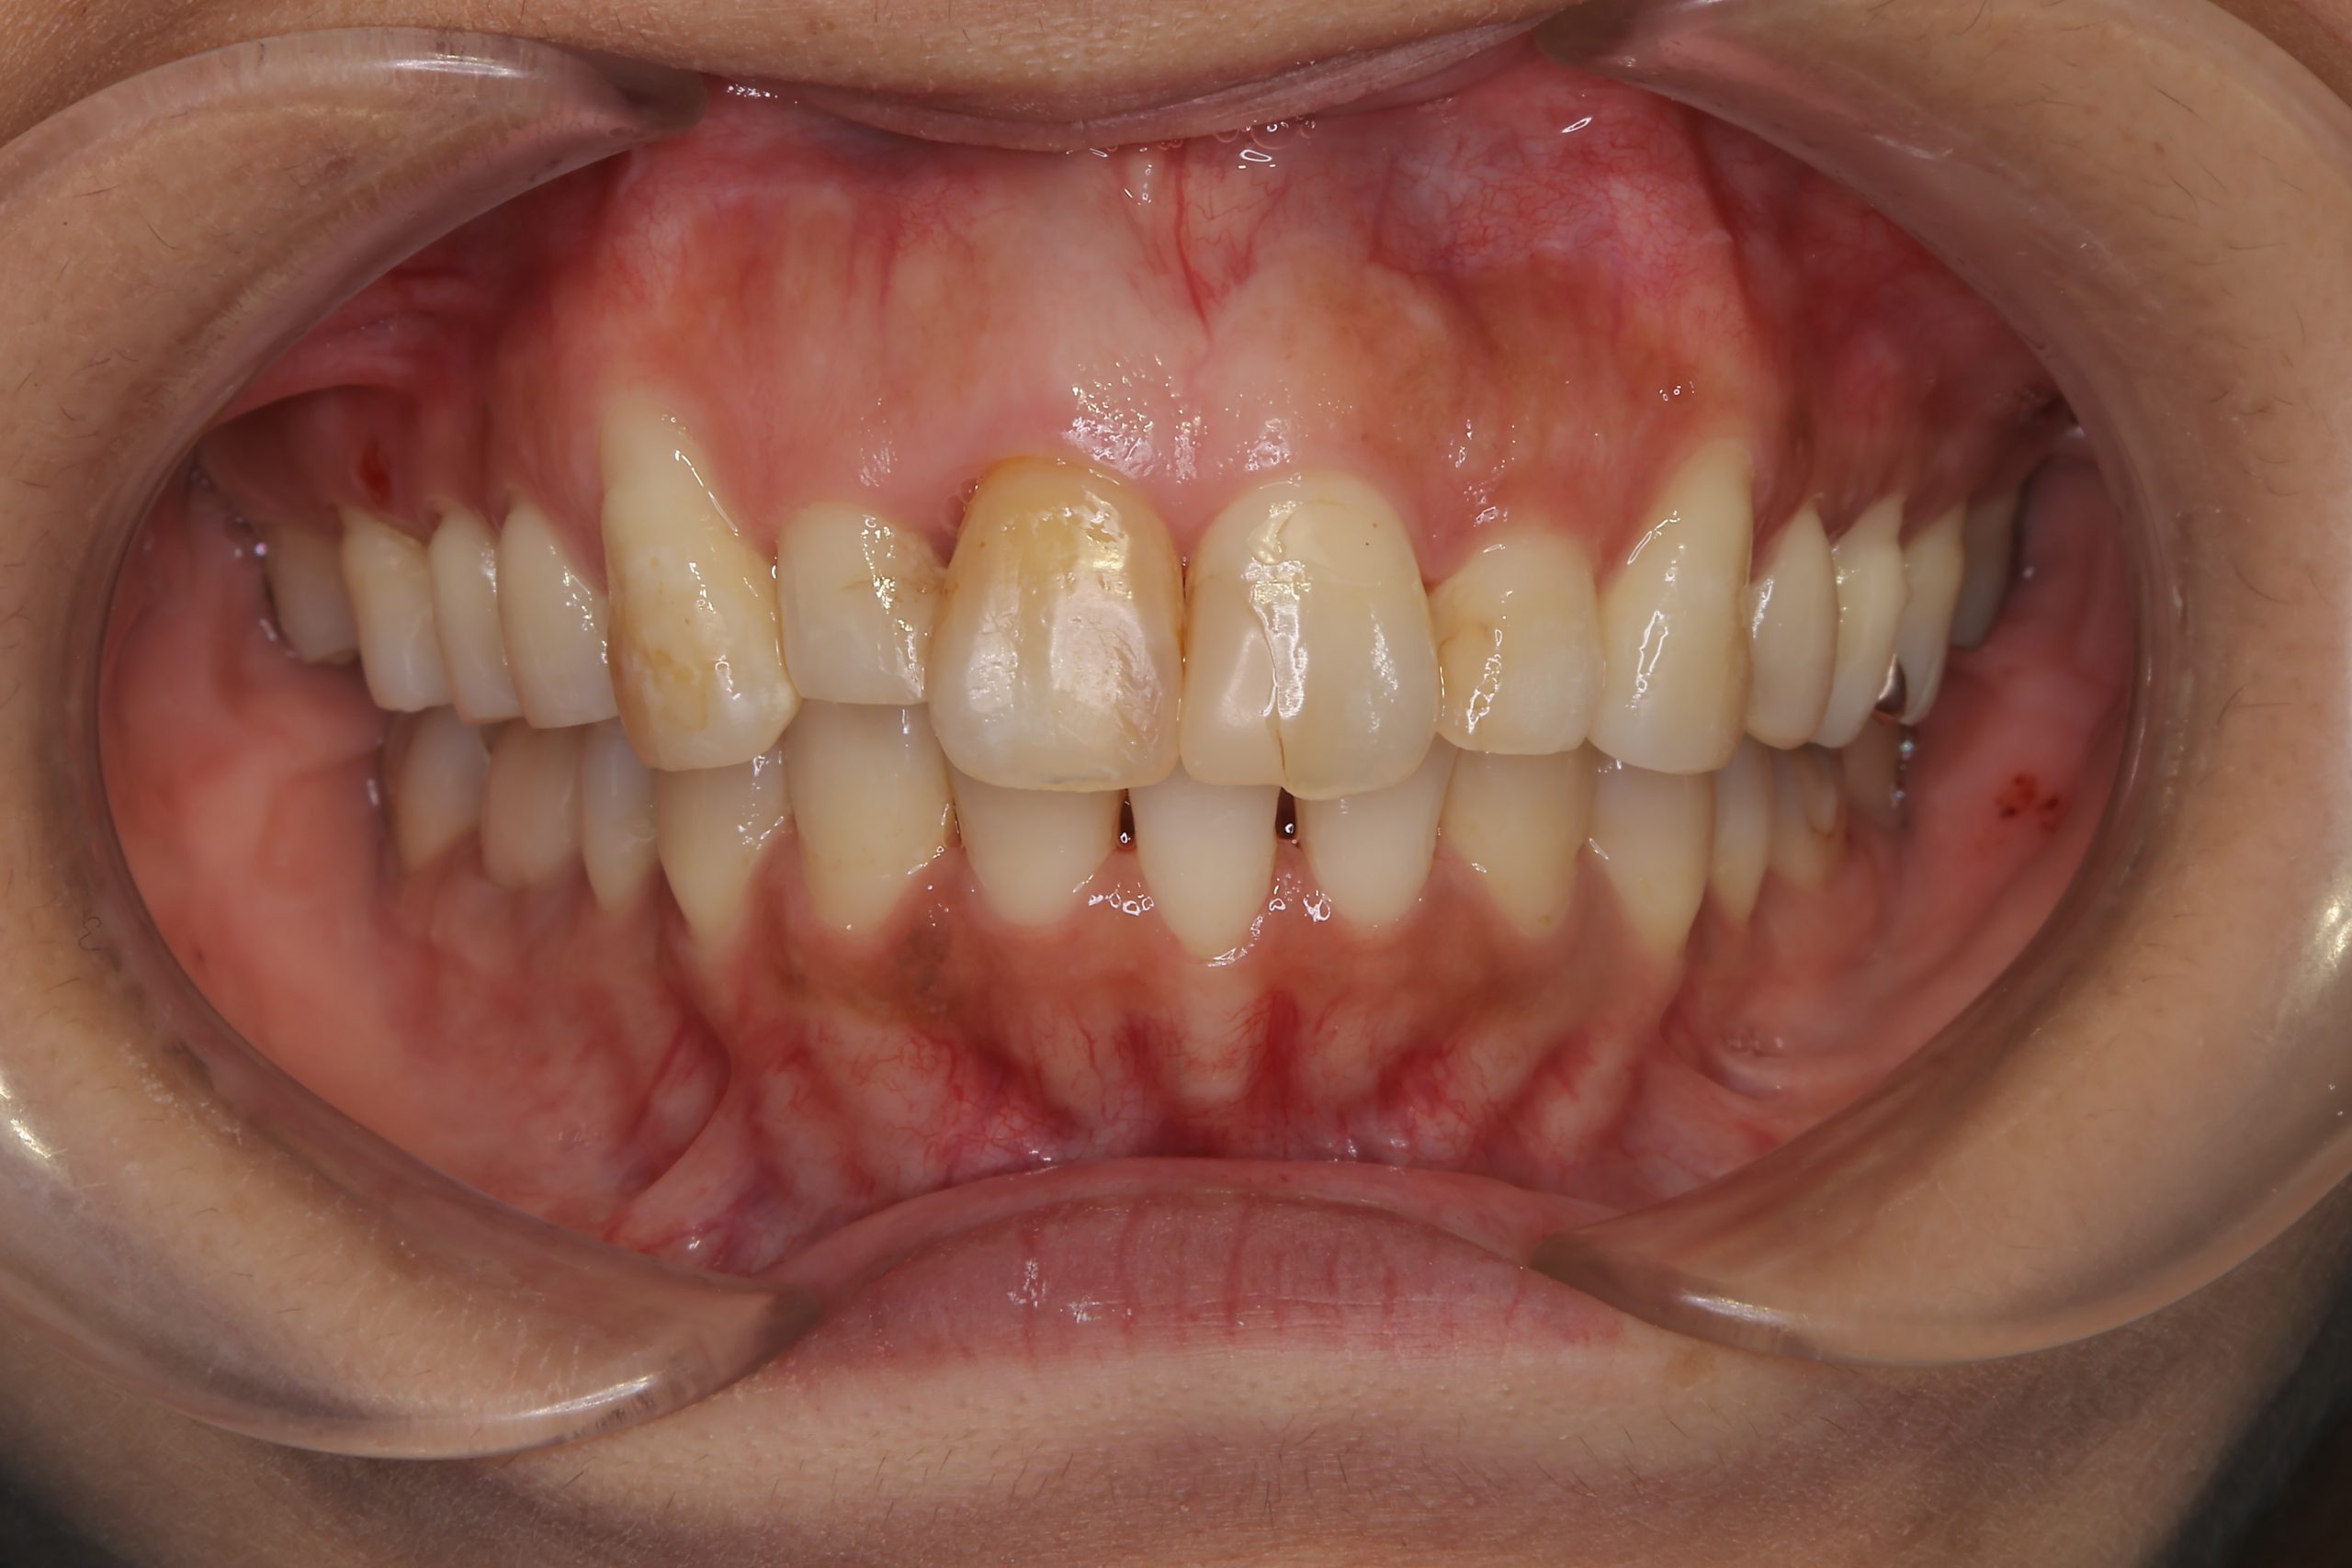

アフター

インビザライン矯正治療|症例_649